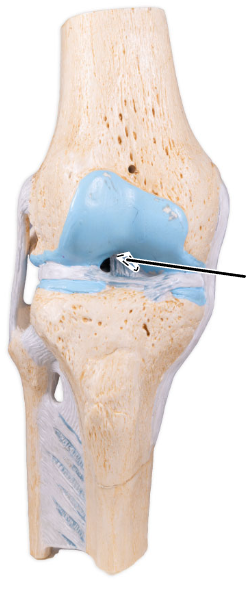

What is the joint shown here?

The tibiofemoral joint.

What is the joint shown here?

The tibiofemoral joint.

What ligament is shown here?

Anterior cruciate ligament.

What ligament is shown here?

Anterior cruciate ligament.

What does the anterior cruciate ligament prevent?

The anterior cruciate helps prevent anterior sliding of the tibia.